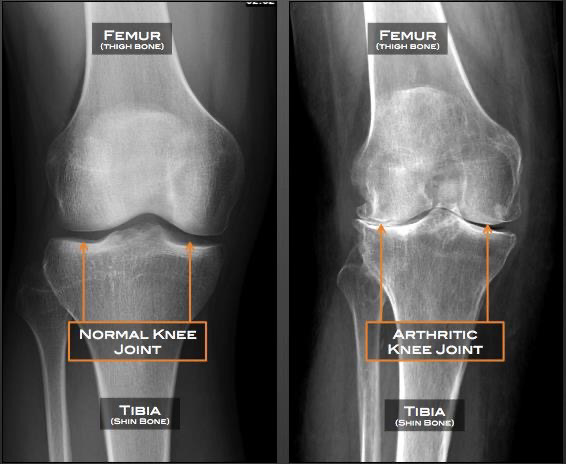

Nivelrikko (osteoarthritis, OA) on ikääntyneillä eniten toimintakykyä häiritsevä sairaus. OA johtuu nivelruston ja sen alla olevan luun hajoamisesta. Nykyään uskotaan, että rustonalaisen luun verisuonten invaasio, jota edustaa H-tyypin verisuonten muodostuminen ja poikkeava luun uudelleenmuodostus ovat ratkaisevan tärkeitä OA:n kehittymiselle.

Väestön ikääntyessä etenkin isojen nivelien nivelrikkojen esiintyvyys on dramaattisesti lisääntynyt. Yleisimmät oireet ovat nivelkipu ja -jäykkyys. Nivelrikon ensisijainen lääke on parasetamoli. Jos sen teho ei riitä, siirrytään tulehduskipulääkkeisiin ja edelleen tekonivelleikkauksiin.

Parantavaa tai taudin etenemistä estävää lääkehoitoa OA:lle ei ole. Tekonivelleikkaus on oireenmukaista hoitoa,

jossa luu korvataan metallilla.

Uudet tutkimukset ovat osoittaneet, että OA:lle voi olla olemassa myös parantavaa hoitoa. Ajatuksen takana uusi

tutkimushavainto, jonka mukaan rustovaurion tärkein syy on riittämättömän hapen saanti.

Se on mahdollista korjata ylipainehoidolla, HBA.